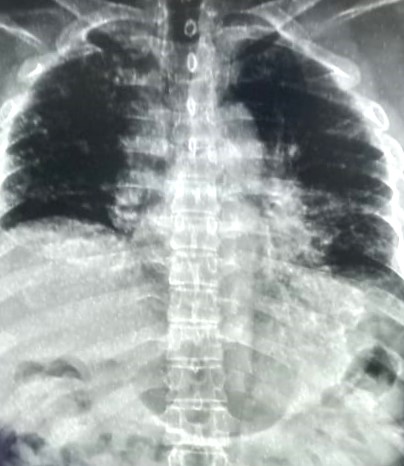

| 318 | IGGMC, Nagpur, Nagpur | P2 | 29-4154 | Tahera Bee | Consent taken on Paper | 70 Yrs. |

Provisional Diag : Post TB Bilateral Bronchiectasis

Final Diag : Post TB sequalae, Bilateral Bronchiectasis In Lower Lobe With Type 1 Respi Failure With Sepsis With Septic Shock With SYST HTN |

Post TB Sequelae | Abnormality visible on x-ray |